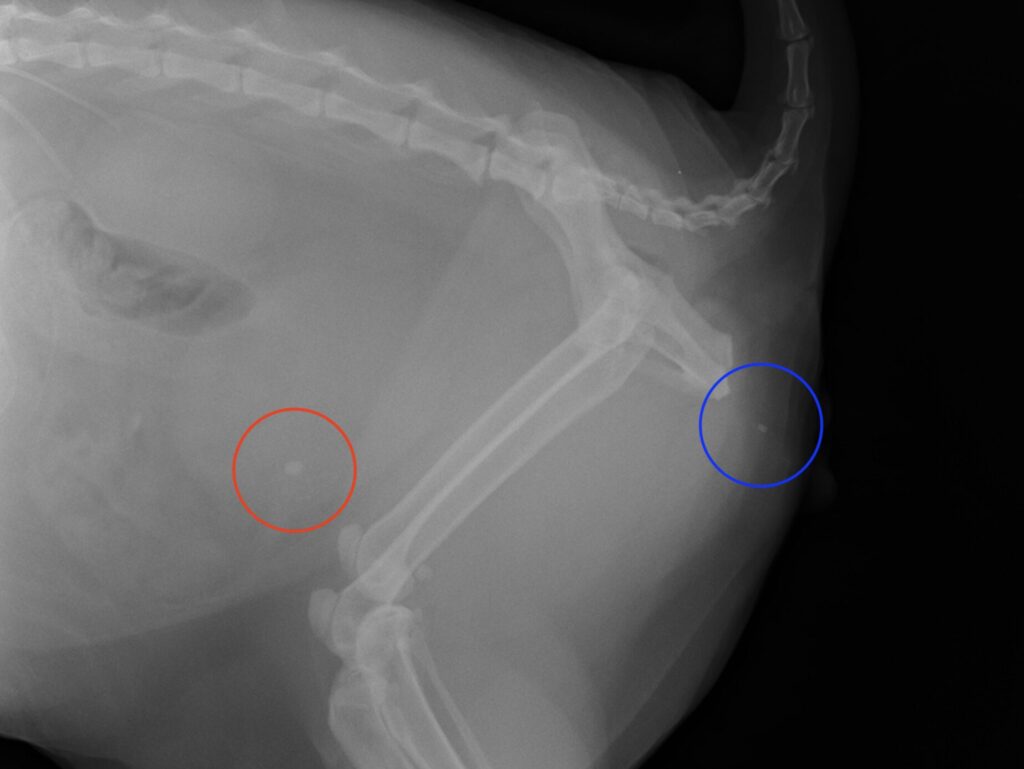

*青枠;尿道に詰まっている小さな石です。